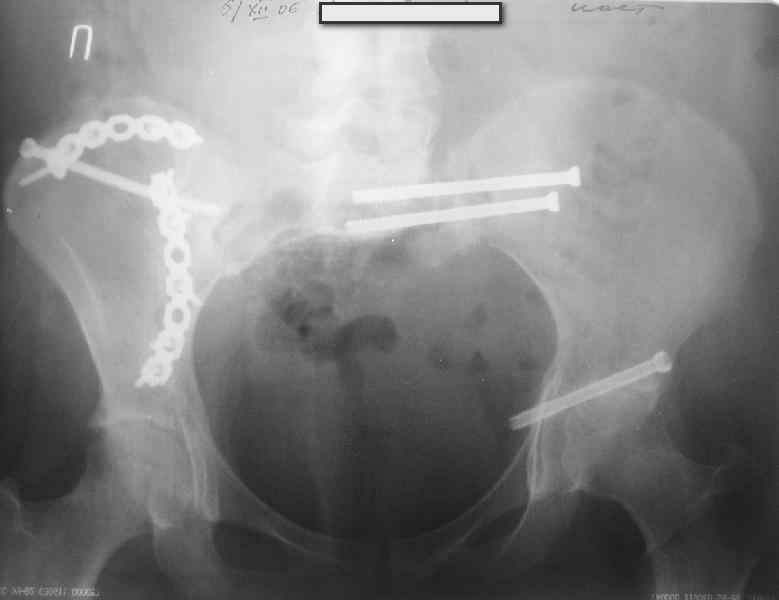

Молодая девушка 19 лет, травма 1 год назад, тогда же прооперирована.

В настоящее время имеются ноющие боли в области крестца слева, нарушение походки, ощущение неуверенности, слабости в левой нижней конечности, неврологически -непостоянные парестезии в левой нижней конечности. Ходит с дополнительной опорой, страдает от ожирения.

В приложении снимки при поступлении и послеоперационные год назад.

Могу сказать одно: миграция винтов и нестабильность синтеза левого подвздошно-крестцовогоо сочленения очевидна.